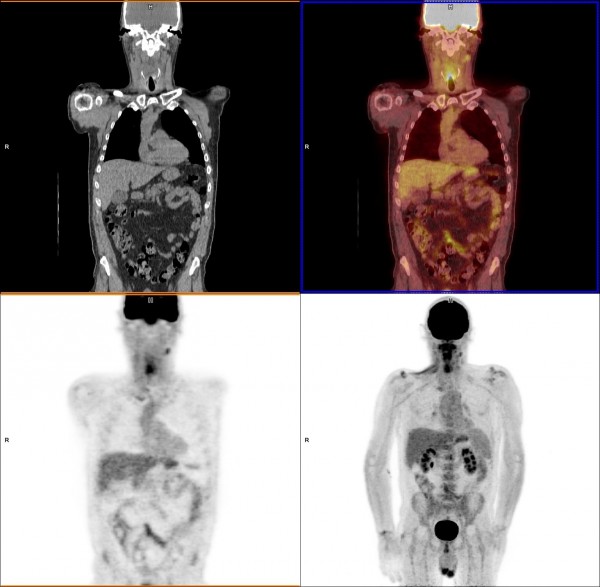

The beauty of the Axumin PET scan is that it offers the possibility to detect small metastatic lesions with PSA levels in the range of 1 to 10 in the lymph nodes. What Are Side Effects of Axumin. So he did Axumin PET and MRI but two scans show different results.

This means that a negative Axumin PETCT scan does not rule out that you have recurrent prostate cancer and a positive Axumin PETCT scan does not confirm that you have recurrent. This means that a negative Axumin PETCT scan does not rule out that you have recurrent prostate cancer and a positive Axumin PETCT scan does not confirm that you have recurrent. Historically simple bone scans and CAT scans required PSA levels in the 10 to 50.

Axumin fluciclovine F 18 injection is a diagnostic imaging agent sometimes called a radiotracer. Studies show the Axumin scan incrementally more sensitive than the C11 scans especially at earlier stages of recurrence or persistence in my case. Learn more about imaging with PYLARIFY now.

Axumin is indicated for Positron Emission Tomography Computed Tomography PETCT imaging in men with suspected prostate cancer recurrence based on elevated blood. For years we have been able to detect. I was diagnosed with gleason 6 prostate cancer 5 years ago.

Cancers Free Full Text 18f Fluciclovine Pet Ct Improves The Clinical Management Of Early Recurrence Prostate Cancer Patients Html

Biomedicines Free Full Text Detection Rate And Clinical Impact Of Pet Ct With 18f Facbc In Patients With Biochemical Recurrence Of Prostate Cancer A Retrospective Bicentric Study Html